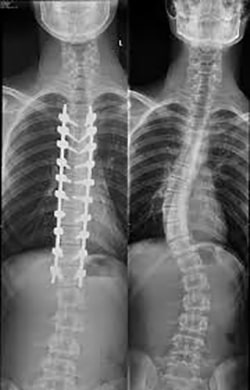

متخصص ارتوپد برای اطمینان از صحت تشخیص از پشت شما بهوسیله اشعه ایکس عکسبرداری میکند.

بهوسیله عکس گرفتهشده با اشعه ایکس شکل، جهت، محل و زاویه انحنای ستون فقرات تشخیص دادهشده و مشخص میشود. نام پزشکی زاویه انحنای ستون فقرات “زاویه اسکولیوز” است.

عمل جراحی

اگر رشد کودک شما متوقف شده و انحراف ستون فقرات (اسکولیوز) وی شدید باشد یا درمانهای انجامشده ناموفق بوده باشد عمل جراحی اصلاحی پیشنهاد میشود. نوع عمل جراحی به سن کودک بستگی دارد.

معمولاً برای بزرگسالان در مواردی که انحنای ستون فقرات زیاد و جدی است عمل جراحی توصیه میشود؛ بهخصوص اگر بیماری بهطور قابلملاحظهای تشدید شود، درد کمر به دلیل وضعیت غیرعادی بدن آزاردهنده باشد و یا اعصاب در اثر فشار ستون فقرات تحت فشار باشند.